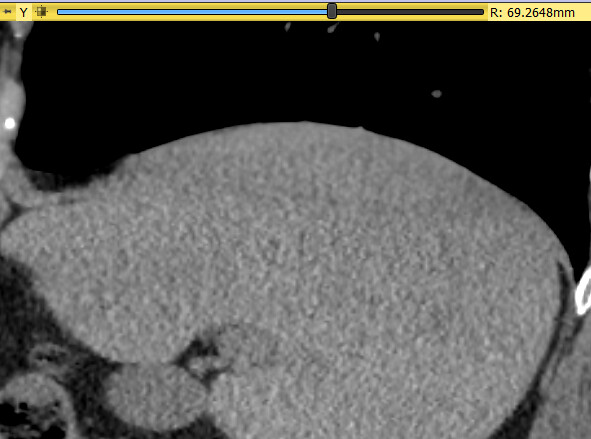

Moreover, as you can see in the photo attached, in some areas, it is very difficult to distinguish between diaphragm and other structures, such as liver and spleen.

immagine